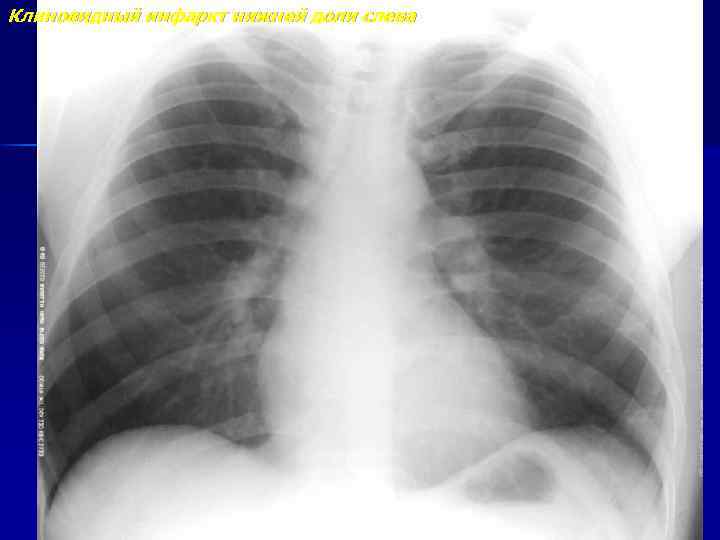

Клиновидный инфаркт нижней доли слева